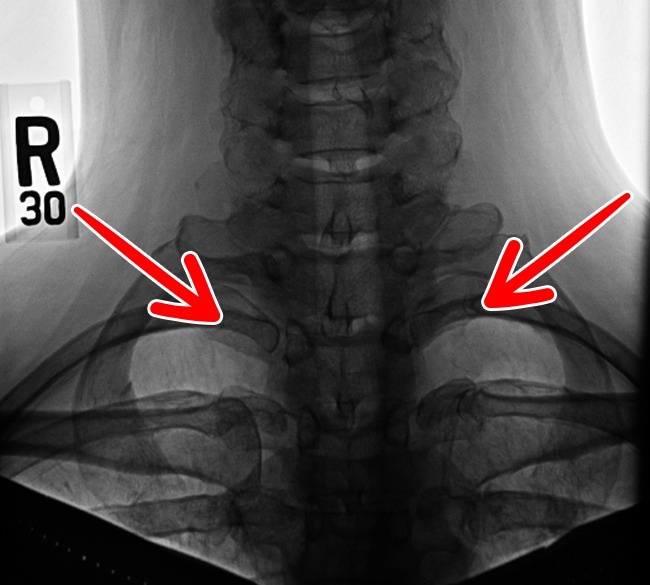

3. Neck rib

This rib appears only in 1% of the population. It can often cause nerve and artery problems.